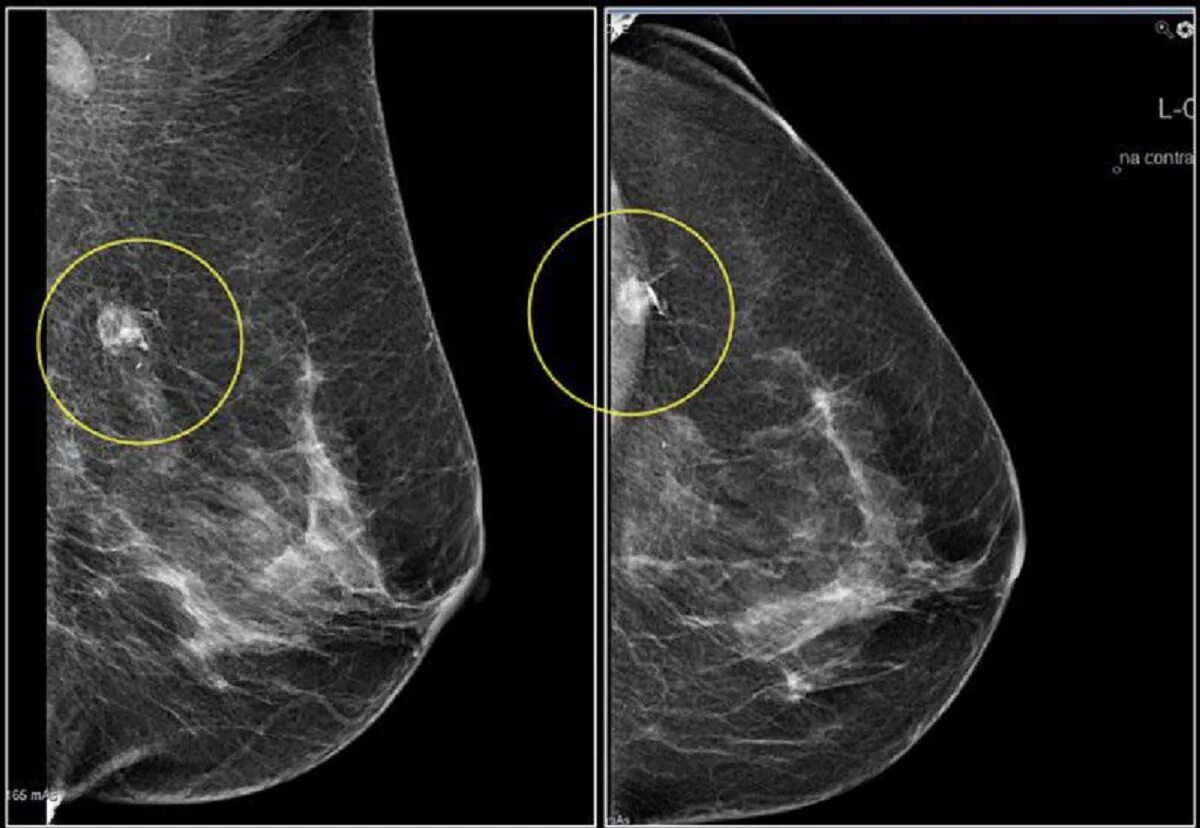

Сгруппированные микрокальцинаты